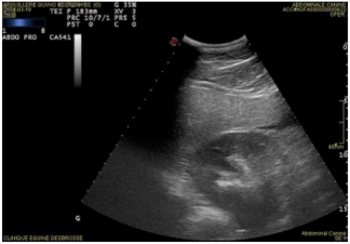

Prise en charge des coliques sur le terrain

L’urgence la plus rencontrée sur le terrain reste la colique. Il est indispensable […]